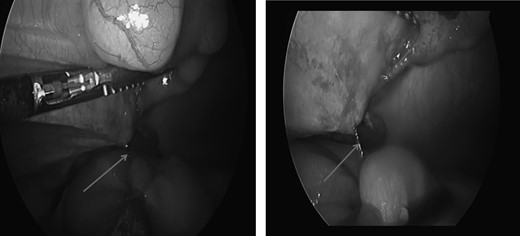

The patient presented to the emergency department on post-operative Day 3 with complaints of nausea, vomiting, abdominal distention and obstipation. Physical examination revealed a tender and distended abdomen, further evaluation with cross-sectional imaging revealed a transition point in the right lower (Fig. 1). He subsequently underwent diagnostic laparoscopy where a free end of the barbed suture was noted to be adherent to the small bowel creating a sharp angulation in the bowel leading to obstructive symptoms (Fig. 2). The suture was lysed close to the peritoneum, which led to the relief of bowel obstruction. Post-operatively the patient had return of bowel function the following day and was discharged home.

Laparoscopic view of self-anchoring suture adherent to the small bowel causing the obstruction.